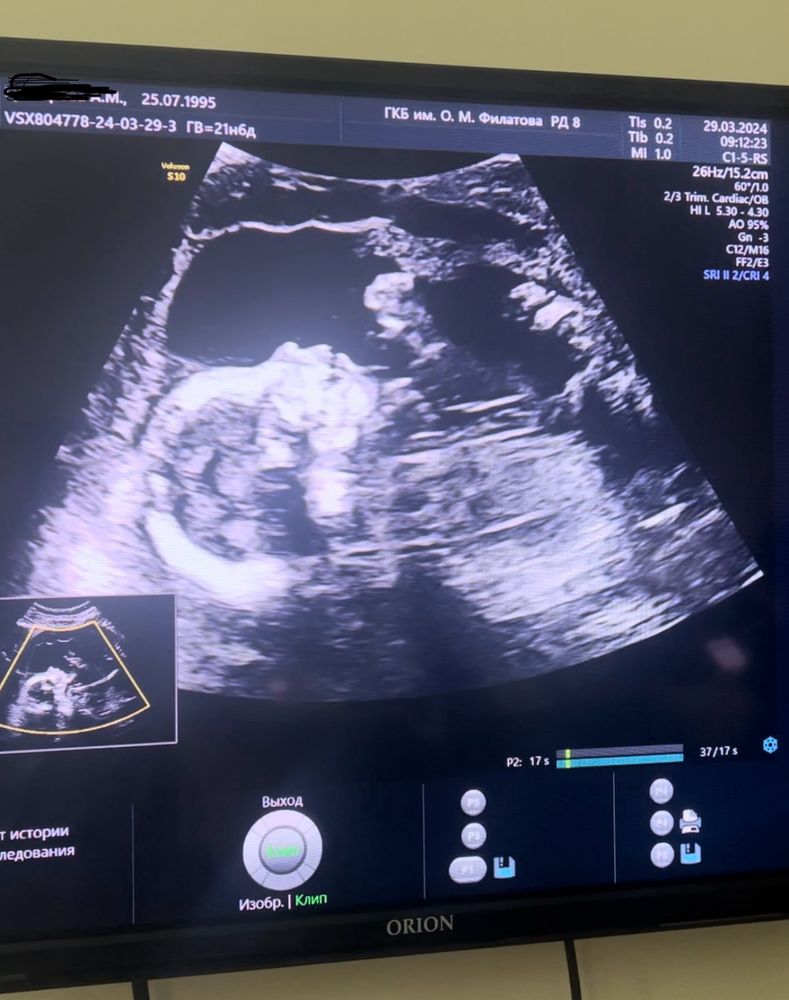

Второй скрининг 🥰 и вопрос по шевелениям

Анализы, скринингиСегодня ровно 20 недель, а вчера прошел второй скрининг - с ребенком все хорошо) подтвердили девочку нам❤️ На последней неделе стала ощущать шевеления, хотя из-за переднего прикрепления плаценты я была уверена, что это произойдет позже. В основном ощущаю пинки, когда лежу на спине, но и сидя в некоторых положениях бывает. В течение дня практически никогда ничего не чувствую, в основном с утра и под ночь начинается гимнастика 🤣 Как часто и интенсивно вы ощущали ребенка на таком сроке?